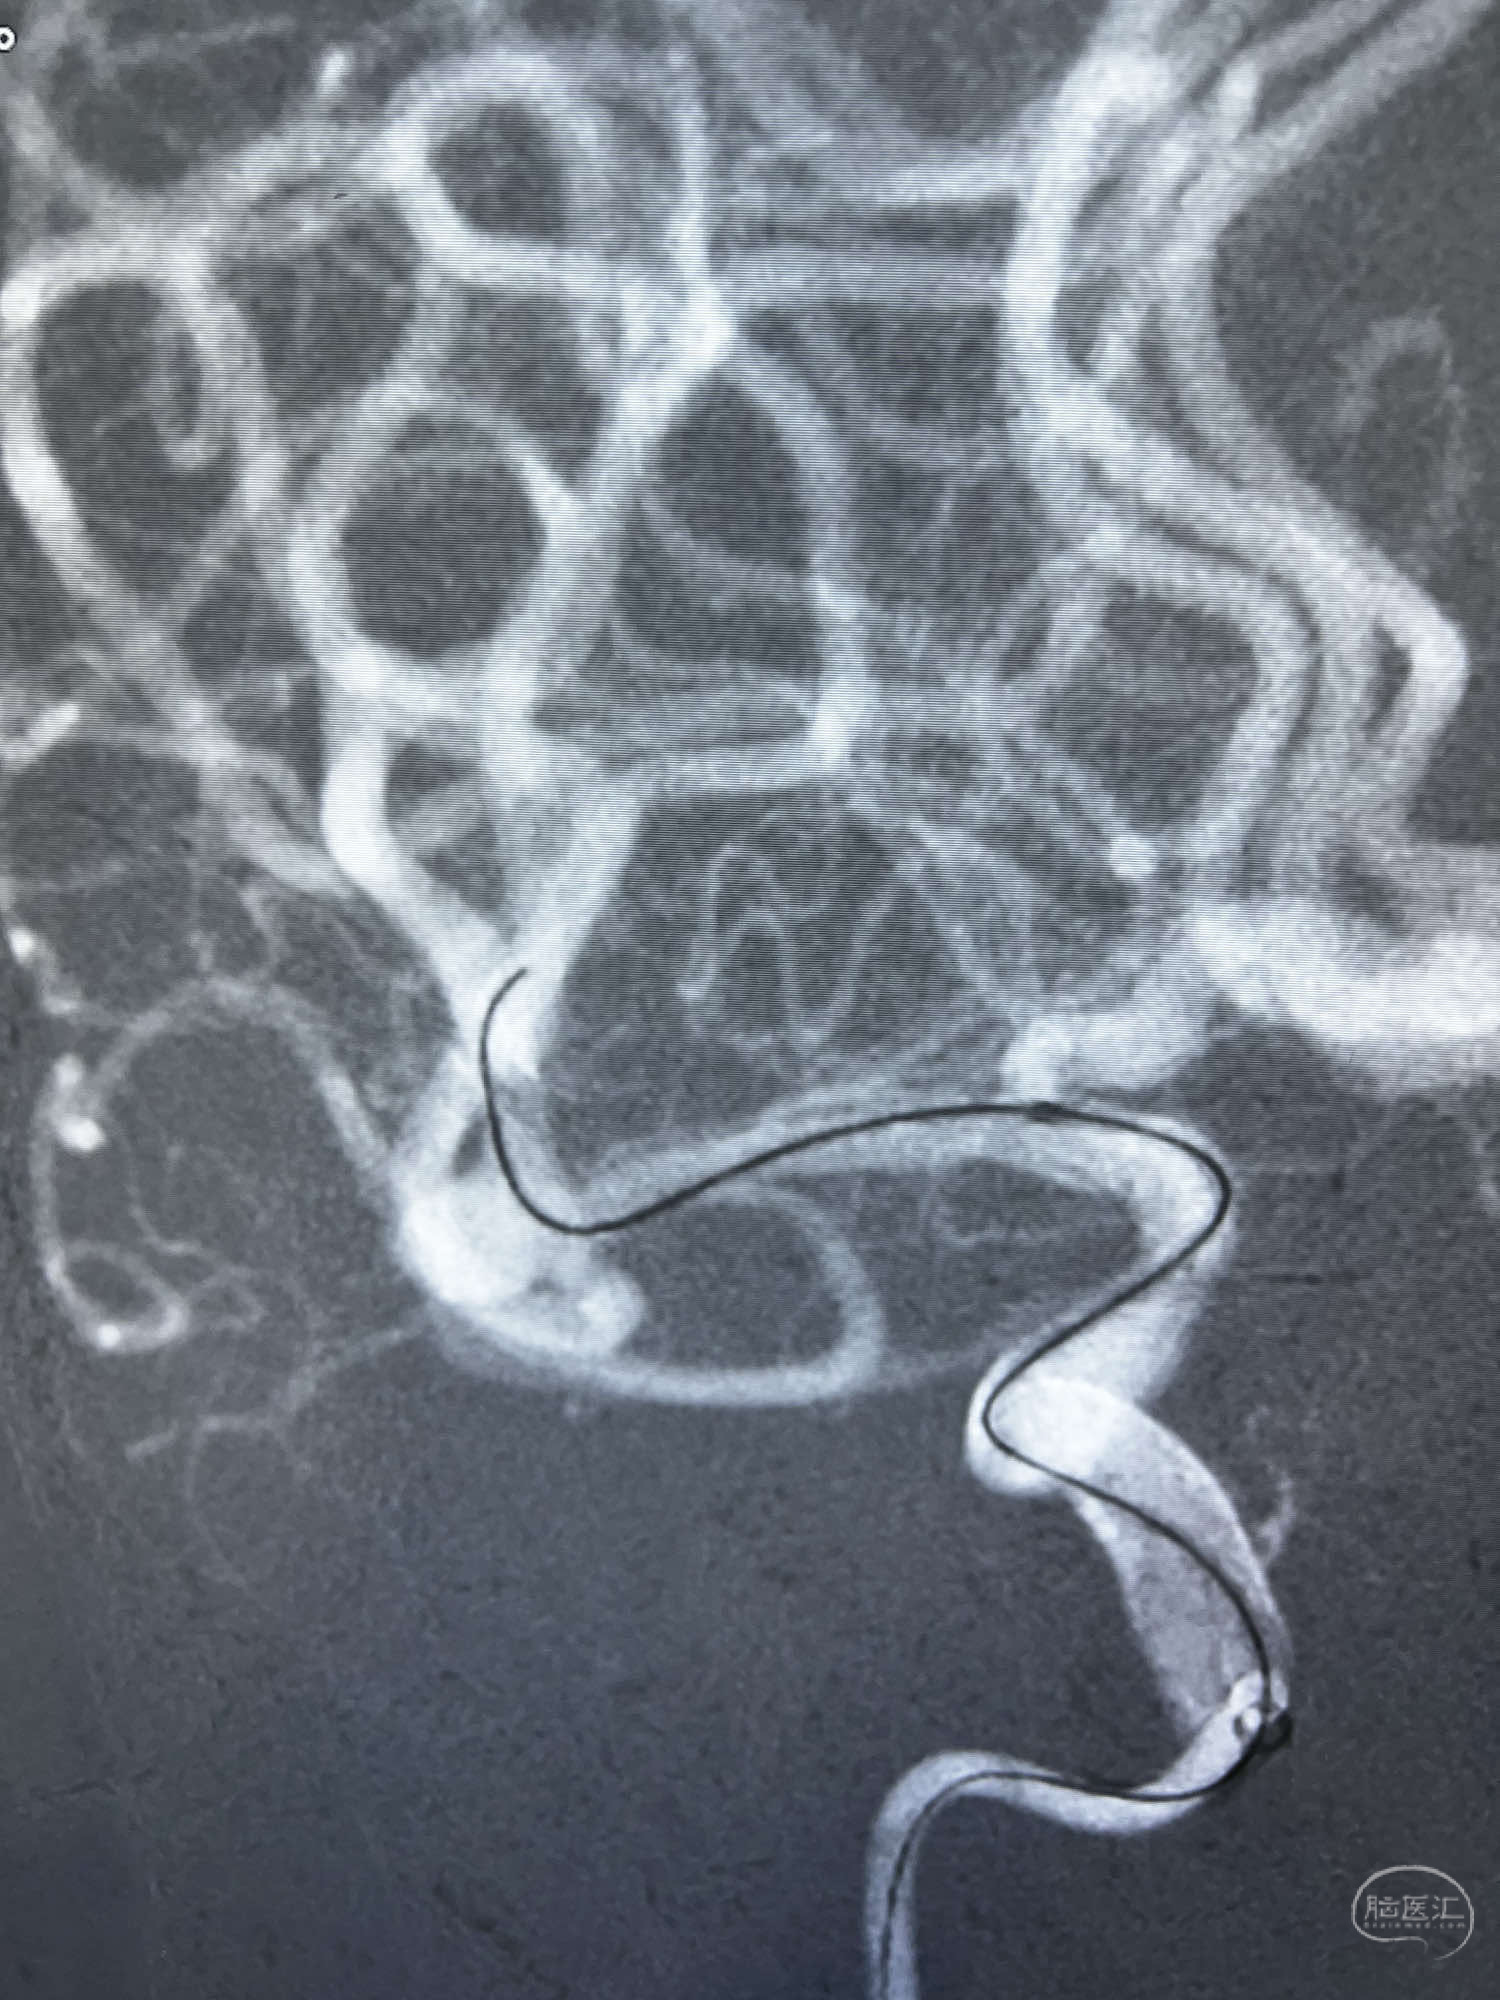

6F Neuromax➕6F115cm 心玮中间导管建立路径,sychro14微导丝➕VIA21超选至动脉瘤体内近中部,WEB5mmx3mm植入动脉瘤。

WEB瘤内扰流装置5mmx3mm经过“种子、萌芽、开花”三个阶段,打开后良好贴壁,动脉瘤内血液滞留,载瘤动脉通畅。WEB一步到位,通过瘤内扰流的方式起到栓塞动脉瘤的作用,避免了应用支架保护分支血管,简化了操作步骤,降低了术中血栓及出血的风险。